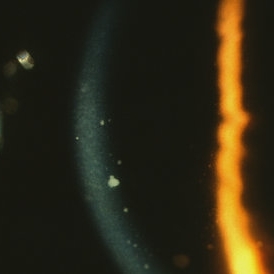

Sarcoidosis Panuveitis Slide 3

Gonioscopic photograph reveals peripheral anterior synechiae with granuloma involving the iris root and Bussaca nodules on the iris surface consistent with granulomatous uveitis.

Photographer: The New York Eye & Ear Infirmary Department of Medical Imaging

Condition/keywords: sarcoid granuloma, sarcoidosis panuveitis